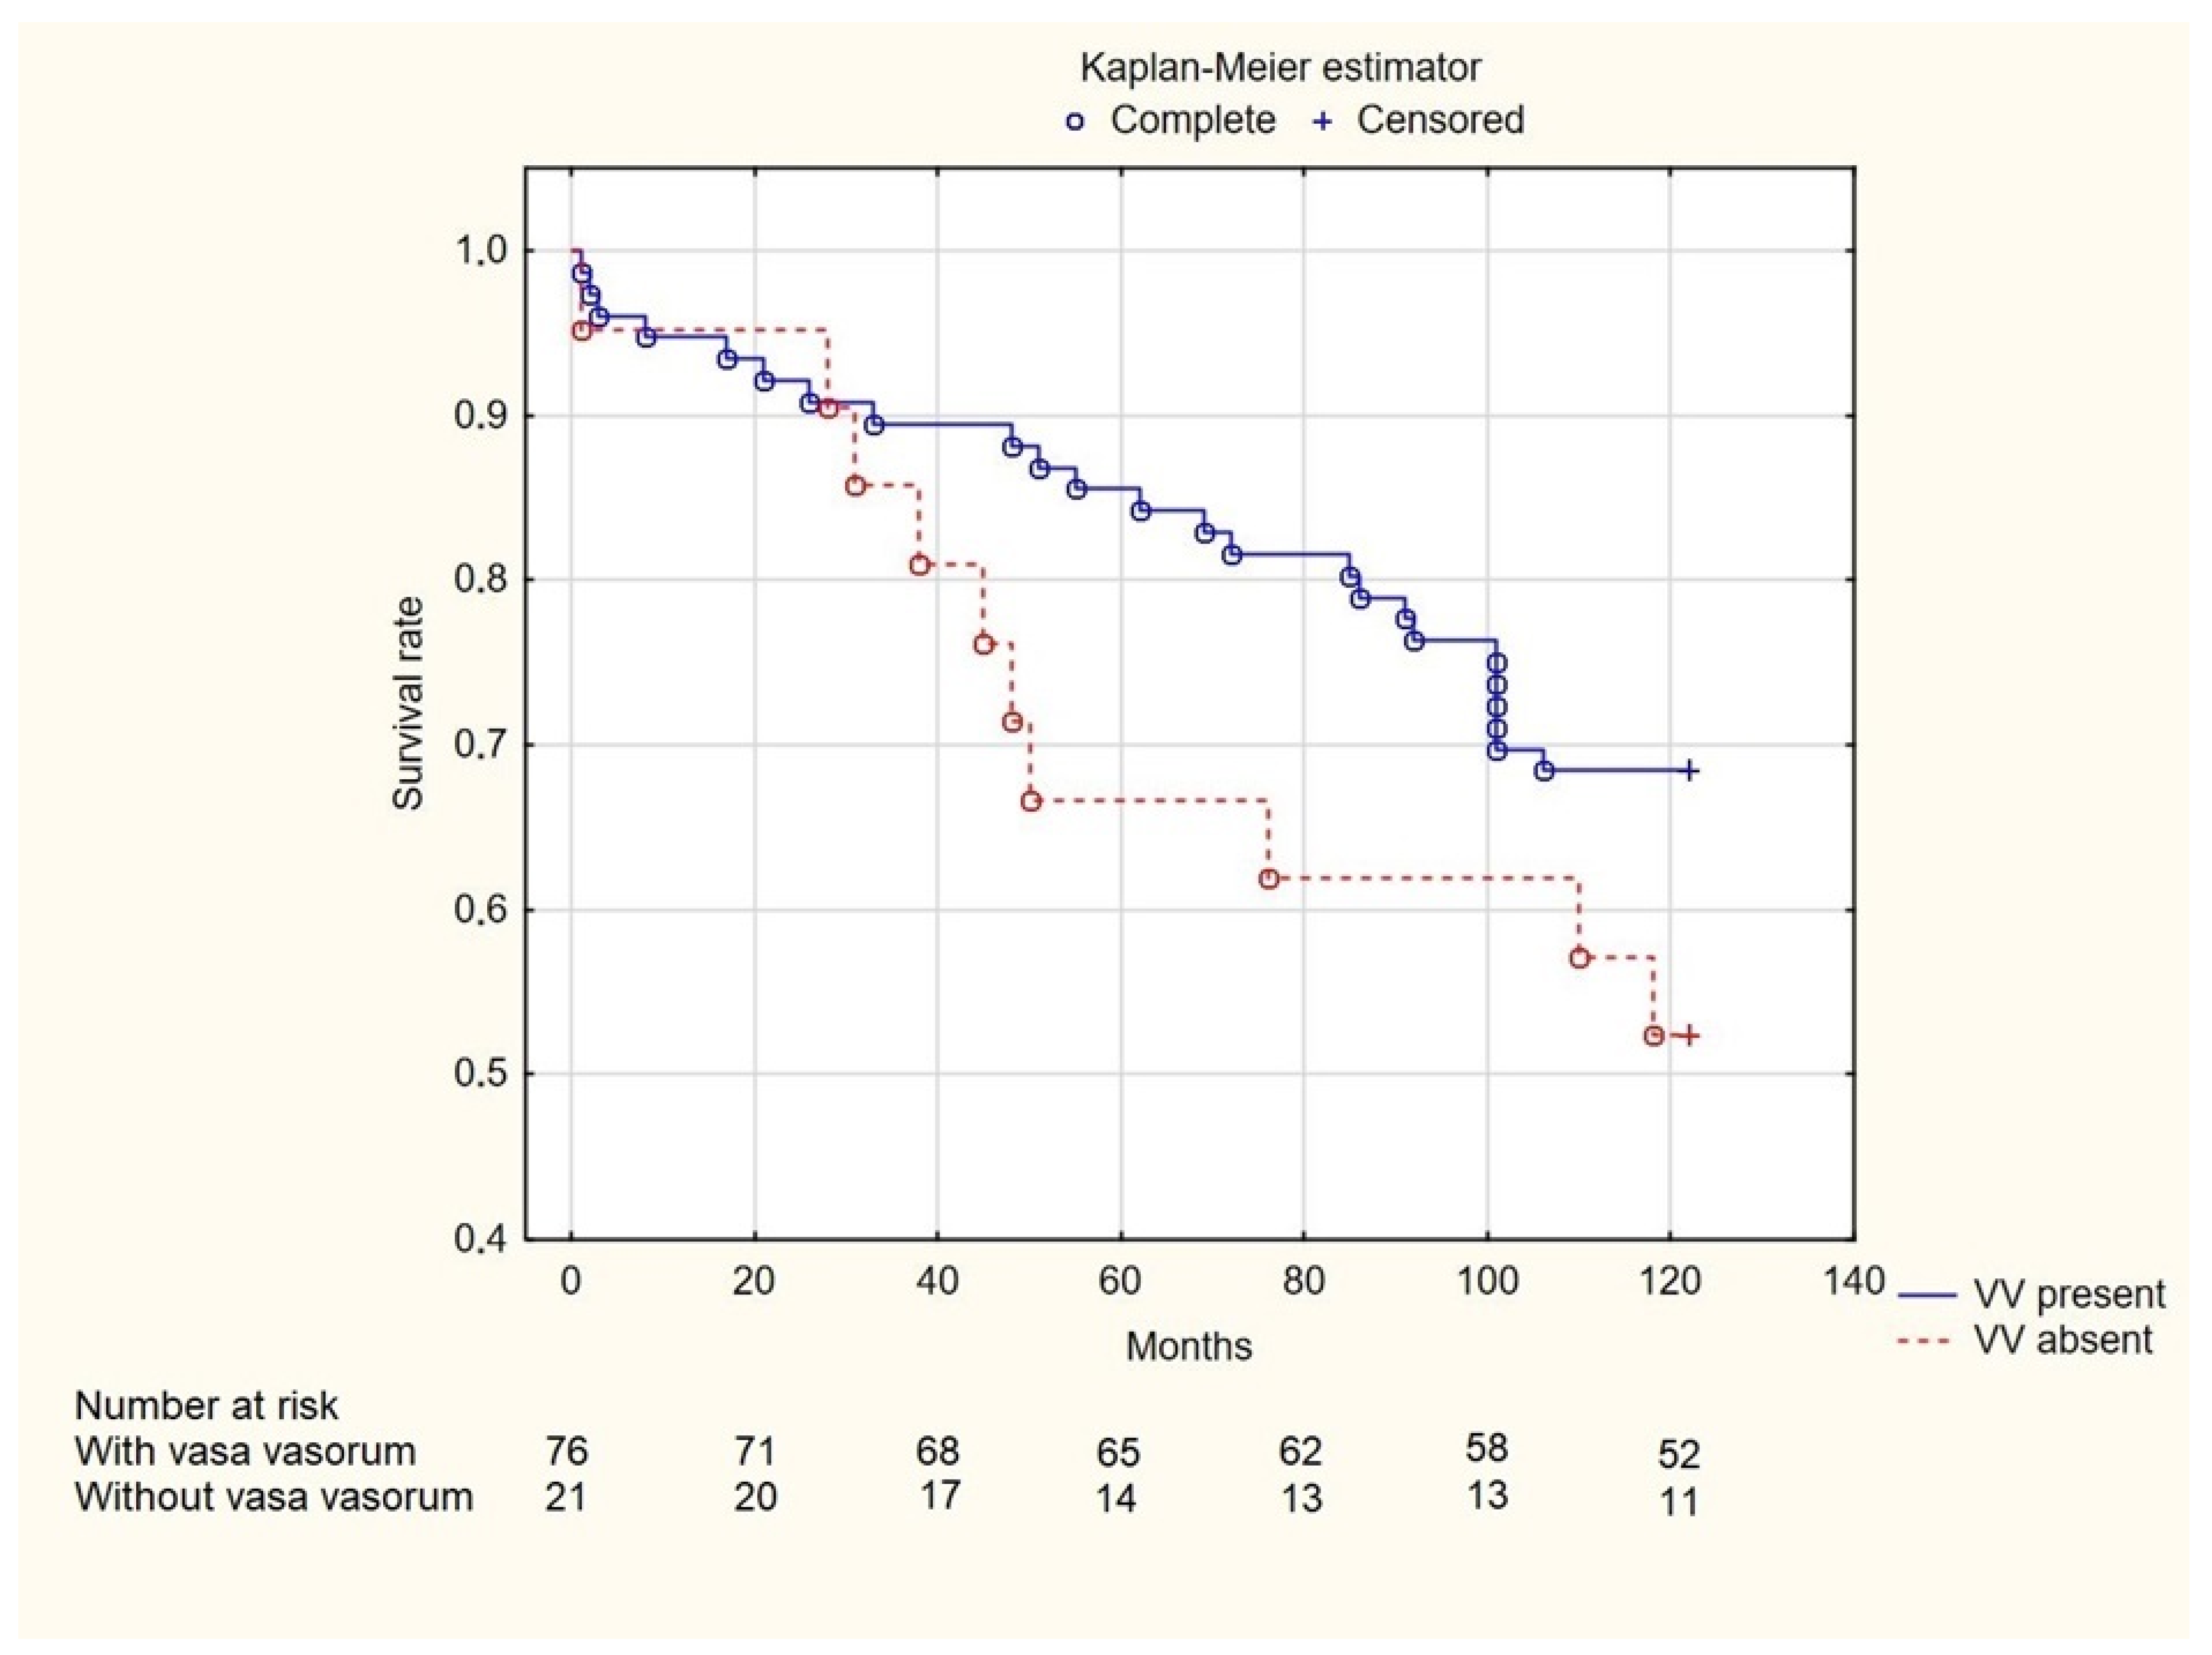

3. Results

4. Discussion

5. Conclusions